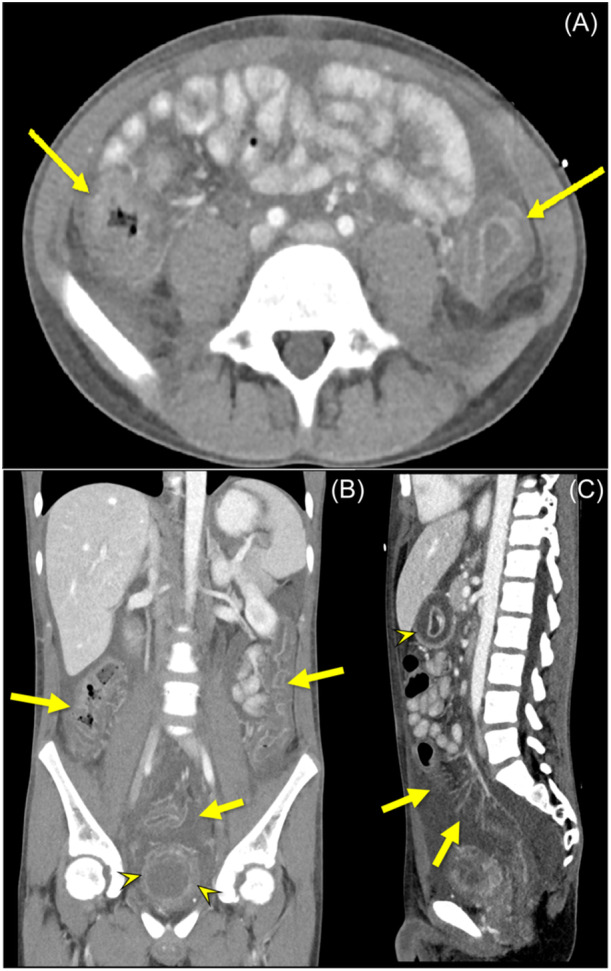

Systemic lupus erythematosus (SLE) is a systemic autoimmune disease that may involve any organ in the body. Inflammation of the bowel wall as a presenting symptom of SLE is uncommon and can lead to delays in diagnosis and treatment. Here, we discuss the case of an adolescent male who presented with weight loss, intermittent fevers, abdominal pain, vomiting, and diarrhea. Initially, inflammatory bowel disease (IBD) was suspected, but endoscopic evaluation did not support this diagnosis. A computed tomography scan of the abdomen revealed signs of serositis, concerning for an inflammatory process and the patient was referred to Rheumatology for further evaluation. Autoimmune serologies were obtained and combined with clinical findings confirmed a diagnosis of SLE. This case advances our understanding of SLE as a multisystemic disease and highlights an unusual presentation involving the gastrointestinal tract, which can mimic IBD and potentially delay the diagnosis and treatment process.